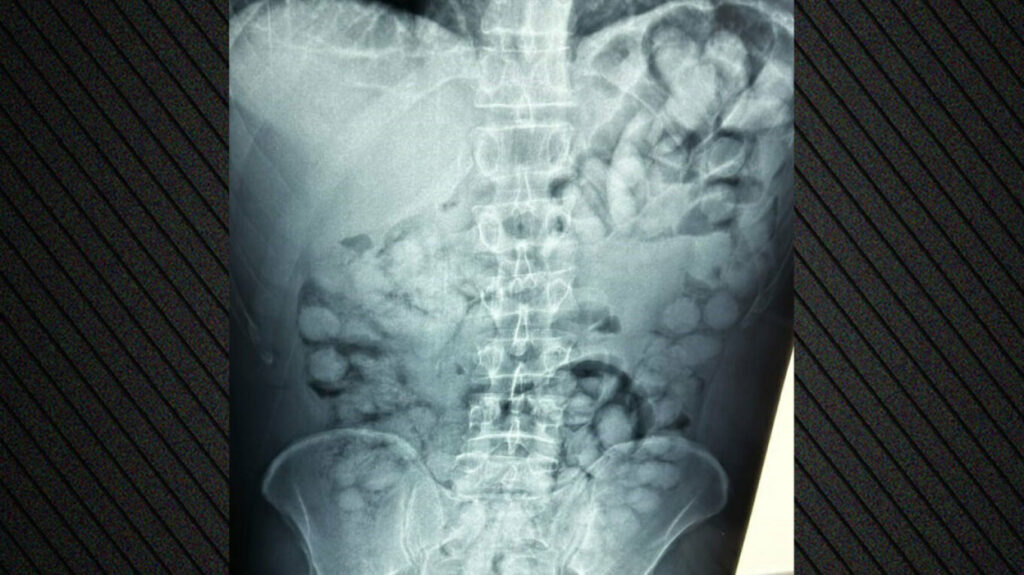

Ένας άνδρας, από τη Βραζιλία, συνελήφθη στο αεροδρόμιο «Ελ. Βενιζέλος», κατηγορούμενος ότι είχε καταπιεί σημαντική ποσότητα κοκαΐνης.

Σύμφωνα με την ΕΛΑΣ, ο άνδρας έφτασε στην Αθήνα, μέσω Παρισιού και στον έλεγχο που διενεργήθηκε, διαπιστώθηκε ότι είχε καταπιεί περίπου 100 συσκευασίες κοκαΐνης.